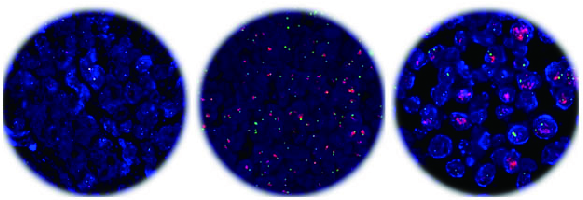

分子病理技术是在蛋白质和核酸等生物大分子水平上,应用分子生物学,生物化学,遗传学和病理学理论、技术及方法研究疾病发生发展的过程。公司(中心)开展全自动免疫组织化学、荧光原位杂交、MicroRNA和lncRNA原位杂交、显微切割等研究与技术服务。引入Aperio公司数字化病理系统,实现组织切片、组织芯片病理诊断及分子病理研究图片的快速扫描诊断与远程会诊。